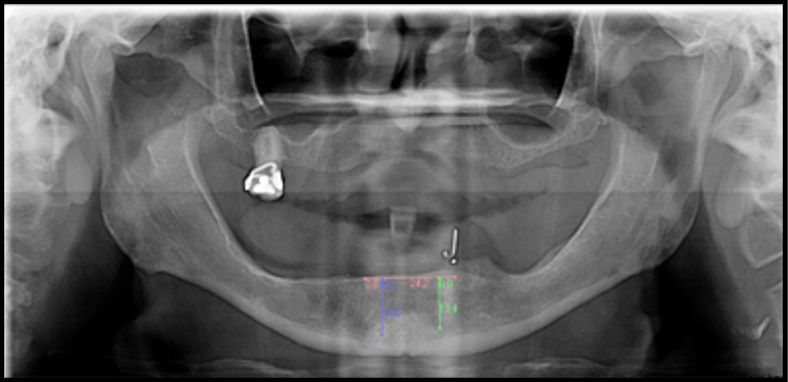

Traditionally, panoramic radiographs/2D images were used for planning the position of implants.22 The patient's existing denture or a duplicate of the existing denture was used as a radiographic guide (by incorporating radiographic markers), and then the denture or duplicate was converted to a surgical guide (Figure 2) and used for placing implants.23 Much information about the dentition, jaws, and joints may be acquired with a small amount of radiation dose from panoramic radiographs (Figure 3).24 However, the panoramic i ages are distorted and magnified. Patient positioning and technical errors further affect the image accuracy.25 It is almost impossible to determine the available bone width and the exact relationships of the neighboring anatomical structures with 2D radiographic images.25,263D radiography provides more accurate representation of the available bone and the surrounding anatomic structures compared with 2D radiography.27 It is critical to assess the position of the inferior alveolar nerve/sinuses while planning the location of implants to prevent injury to vital anatomic structures.28